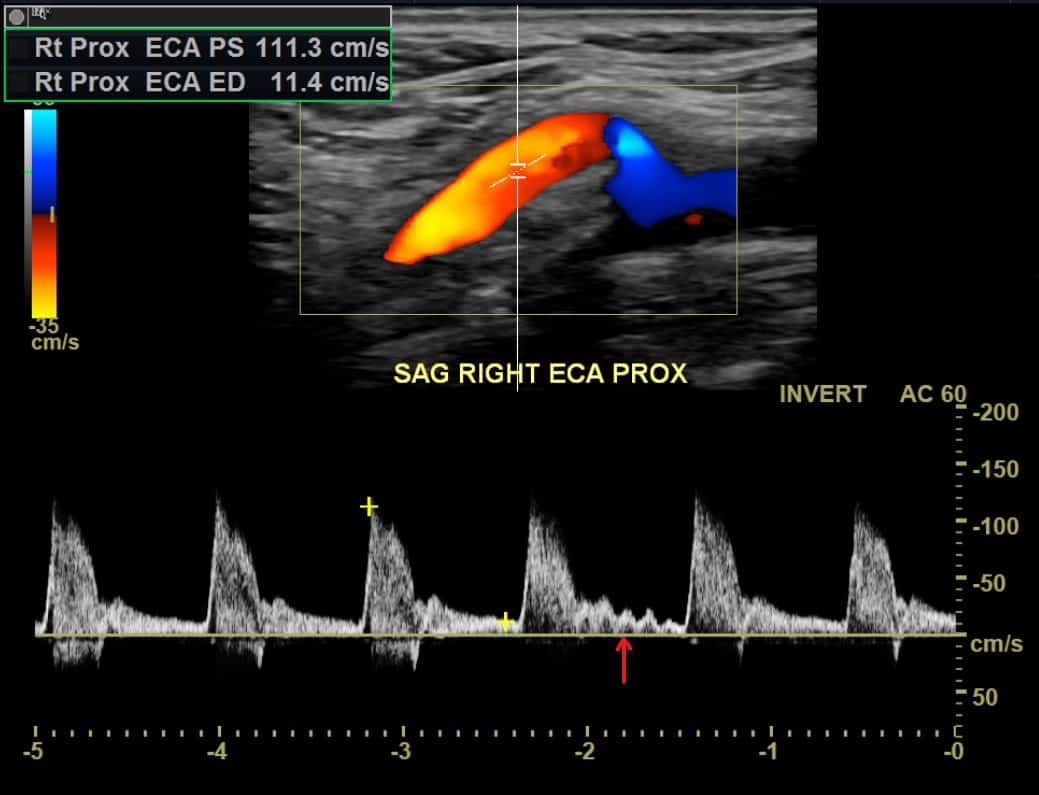

There is another trick we have to identify the external carotid artery. It is called the temporal tap. The sonographer taps gently on the patient’s superficial temporal artery while imaging the external carotid artery. Because the superficial temporal artery is connected to the external carotid artery, the tapping will appear on the ultrasound:

One word of caution, though. If you tap hard enough over someone’s forehead, any tapping will appear on the waveforms 😉

Interestingly, there are no definite ultrasound criteria for external carotid artery stenosis. Publications have suggested criteria.